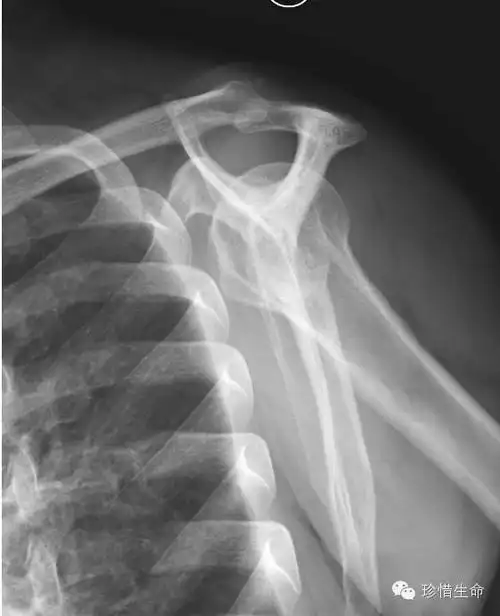

肩关节的x线照片或x线照片.另外一个视图名是冈上出口

肱骨x线照片,侧位.

不同肩关节x线投照位ppt课件